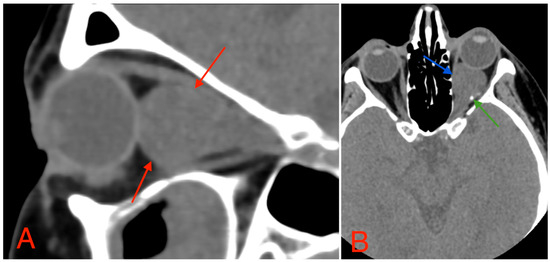

The CT scan revealed a pathological mass in the intraconal space, ~1.5 cm × 2.5 cm × 1.5 cm, which occupied most of the orbit. Noticeable thinning and depression of the rectus muscles of the eye were also noted (Figure 3). A cranial contrast enhanced MRI was conducted the following month, revealing an entirely altered optic nerve affecting the retrobulbar, prechiasmal, and optic chiasm level. A pathological, smoothly contoured mass with cystic changes was described and measured about 5.2 cm × 2.0 cm × 1.9 cm. Greater peripheral contrast accumulation in the pathological tissue extended along the optic chiasm and relatively close to the frontal lobe’s straight gyrus. The pathological mass also extended relatively close to the A1 segment of the anterior cerebral artery and stretched in the direction of the pituitary gland. A lateral depression of the extraocular muscles was also noted (Figure 4). The contrast-enhancing component of the tumor on diffusion-weighted imaging (DWI) sequence showed a restricted diffusion at an apparent diffusion coefficient (ADC) value of 1500 × 10−6 mm2/s, with a b value of 1000 s/mm2. A high T2 signal intensity was also noted.

Figure 3. (A) CT scan of orbits, sagittal plane, 2 mm slice, showing a homogeneous, well-marginated optical nerve tumor with a mass effect and a compression of the rectus muscles of the eye (red arrows). (B) CT scan of orbits, axial plane, 1.25 mm slice, showing an intraconal lesion with intracranial extension, mass effect (blue arrow), and small calcification (green arrow). A mild exophthalmos can also be noted.